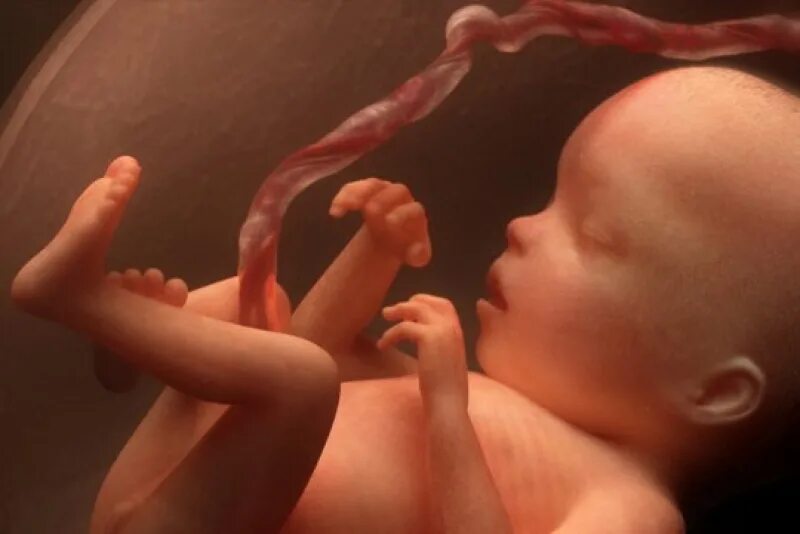

18 недель как выглядит малыш